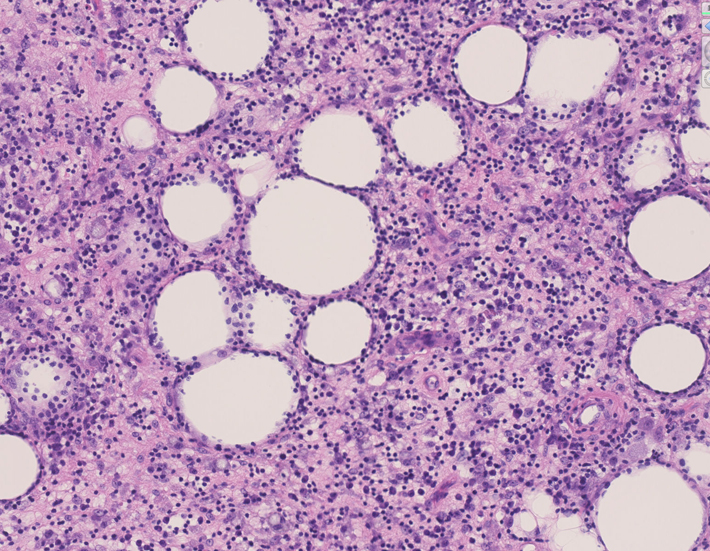

リンパ腫の定義: SPTCLは成熟細胞障害性T細胞(cytotoxic T-cell)由来で、皮下組織に脂肪識炎に似た組織像を呈しながら増殖する悪性リンパ腫。

組織所見*16*17*18

皮下組織に優位な, 小~中型 Tリンパ球の密な浸潤が特徴。ときに大型リンパ球や組織球が混在する。 リンパ球の異型は, わずかなものから明瞭な異型を示す症例までさまざまである。